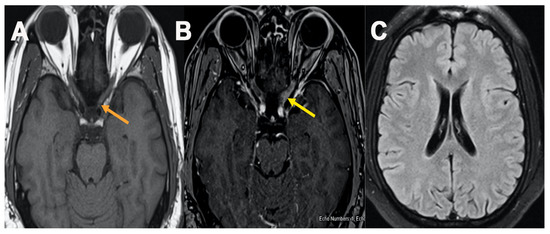

A 42-year-old male presented to the ED with complaints of blurry vision and 3-day left eye pain worsened with movement. Upon examination, diffuse gray field vision in the left eye was noted. The patient received both doses of the Pfizer-BioNTech COVID-19 vaccination 3 months ago. Cranial nerve 3, 4, and 6 examination revealed horizontal diplopia in the left eye. Muscle strength 5/5 bilaterally and reflexes 2+ bilaterally. Further eye examination revealed a positive relative afferent pupillary defect in the left eye with clear disc margins. Orbital MRI revealed left optic nerve enhancement (Figure 3). MRI brain unremarkable. CSF was significant for increased protein. Oligoclonal bands were absent and NMO, MOG antibodies were negative. The patient showed significant improvement at discharge with IV solumedrol and oral prednisone treatment.

Figure 3. MRI orbit Figure 3, axial T1 plain (A) and post contrast fat saturation axial images (B) showed abnormal enhancement within the intracanalicular portion of left optic nerve (B) (yellow arrow), MRI brain axial FLAIR cut at level of lateral ventricle showed no abnormal T2/FLAIR signal changes (C).